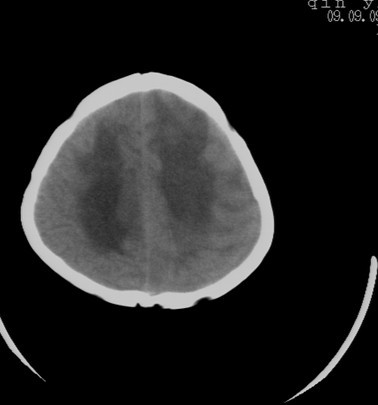

先天性疾病.小脑是正常的,左侧大脑半球发育不良伴有脑肿瘤形成,脑积水.名堂真多。建议mri

先天性疾病.小脑是正常的,左侧大脑半球发育不良伴有脑肿瘤形成,脑积水。建议mri